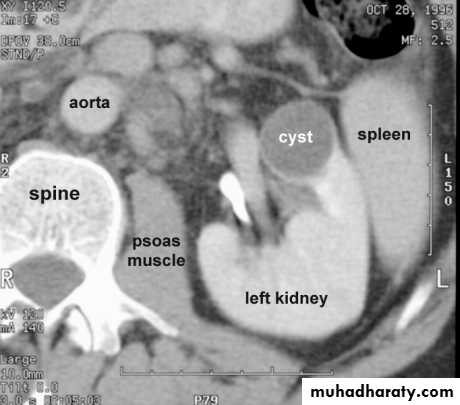

SIMPLE RENAL CYST* Common cause of renal mass .

* Uncommon under age of 30 years , most common over 50 years .

* Single or multiple .

* Usually cortical in origin .

* Varies in size ; few mm to 25 cm .

* Contains straw color fluid , with thin fibrous wall lines by flat epithelium .

* Clinically silent , large cyst can shows palpable mass .

* Calcification is rare , normal renal function .

Renal cyst cont.

KUB :1- Cyst in upper pole displace kidney downward . Cyst at medial surface displace the kidney laterally .with enlarged kidney

2- Smooth local bulge of renal out-line.

3- Calcifications rare 3% usually in hemorrhagic cyst.

Renal S.O.L (cyst)

RENAL CYST

IVU :-* Nephrogram shows filling defect .

*Displacement , elongation & stretching of PCS which depend on size and site of the cyst .

US :-

shows echo-free cystic lesion with posterior enhancement.